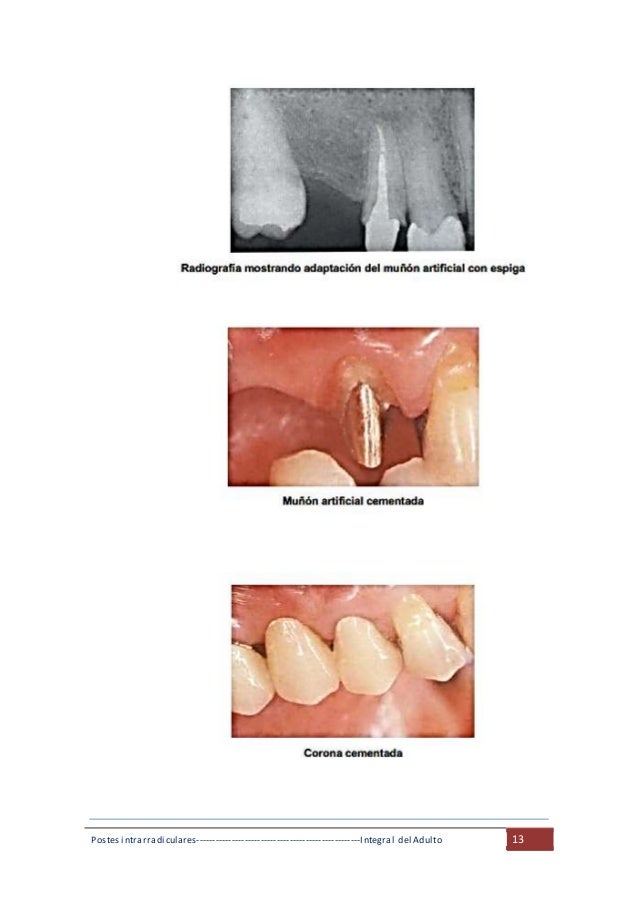

Pernos Intrarradicualres